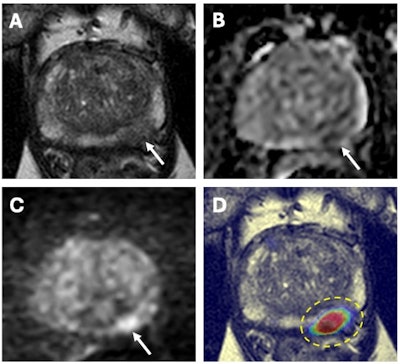

67-year-old male with a serum PSA of 6.5ng.ml. Axial T2W MRI (A) shows a hypointense lesion in the left apical-mid peripheral zone (arrow) which demonstrates focal diffusion restriction on ADC map (B) and high b-value diffusion-weighted MRI (C) (arrows). AI output of a biparametric prostate MRI lesion detection AI model demonstrates high cancer probability within the left apical-mid peripheral zone lesion (dashed yellow circle) (D). MRI/TRUS fusion guided biopsy revealed Gleason 3+4 prostate cancer within this lesion. Images and caption courtesy of the National Cancer Institute.